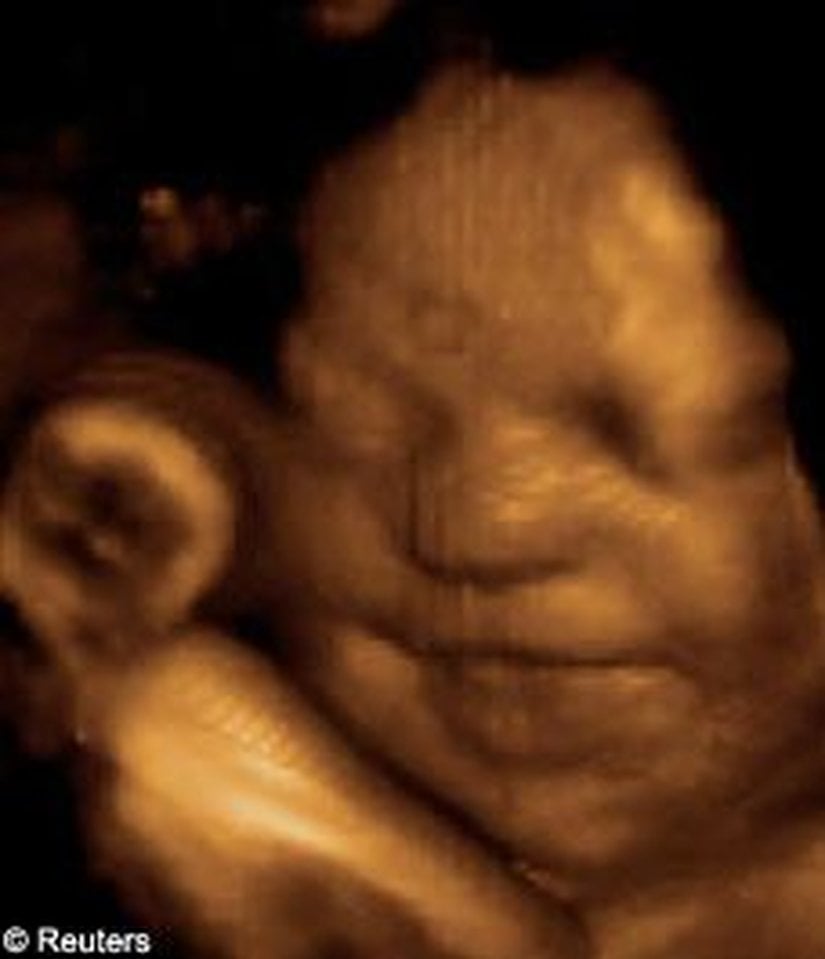

Bu görüntüleme tekniği sayesinde, artık renkli ve çok daha net sonuçlara ulaşabiliyoruz. Bu görseller, bunun en net ispatlarından biri. Ana karnındaki ikizleri çok detaylı bir şekilde görüntülemek artık mümkün. Hem de o, uzaktan odaklanılmış bir kare. Aşağıdakiler, ne demek istediğimizi daha net anlatacaktır:

3D ultrasonlarda, birden fazla açıdan 2 boyutlu görüntüler çekiliyor ve sonrasında bilgisayar yardımıyla 3 boyutlu bir görsele dönüştürülüyor. Bu sayede bebeğinizin sadece bir kesidini değil, 3 boyutlu bir görüntüsünü elde etmeniz mümkün oluyor.

4D ultrasonlarda ise, 3D olan görüntüler zamana yayılmış bir şekilde kaydediliyor. Bu sayede bebeğin hareketlerini tıpkı bir video izler gibi görmeniz mümkün oluyor. Bu sayede bebeğin gözlerini açıp kapaması, gülümsemesi veya parmağını emmesi gibi olayları çok net bir şekilde görüntüleyebiliyorsunuz.

Bu yeni teknik, sadece ebeveynlerin yavrularını daha kısa sürede, daha net görmelerini sağlamayacak, aynı zamanda birçok hastalığın çok daha erkenden teşhisine katkı sağlayacak. Bu yeni yöntemler kullanılarak fetüsleri çok daha yakından görmek ve bu sayede doğuştan gelen bazı hastalıkları (tavşan dudaklılık, omurilik sorunları, vb.) çok daha erkenden tespit edebilmek mümkün oluyor. Şimdilik bu gelişmiş yöntemler, "sıradan doğum kontrollerinde" rutin olarak uygulanmıyor; ancak bir şüphe doğarsa uygulanabiliyor.